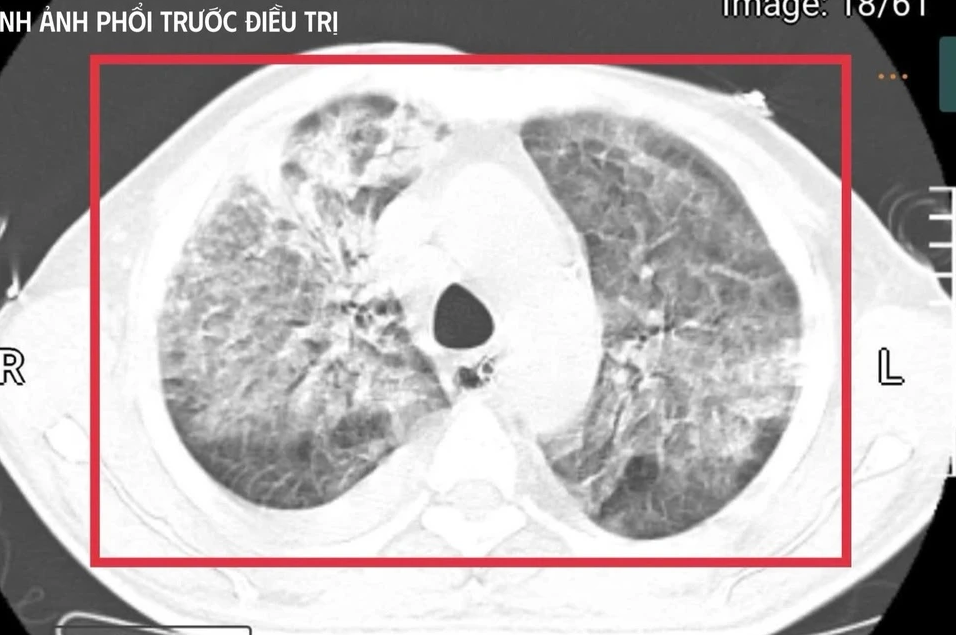

Tại đây, bệnh nhân được đặt nội khí quản thở máy; kết quả cấy máu xác định nhiễm Burkholderia pseudomallei – tác nhân gây bệnh Whitmore. Dù được điều trị ban đầu, tình trạng vẫn diễn tiến nặng nên gia đình xin chuyển về Việt Nam để tiếp tục điều trị.

Bệnh nhân được xác định nhiễm Burkholderia pseudomallei – tác nhân gây bệnh Whitmore